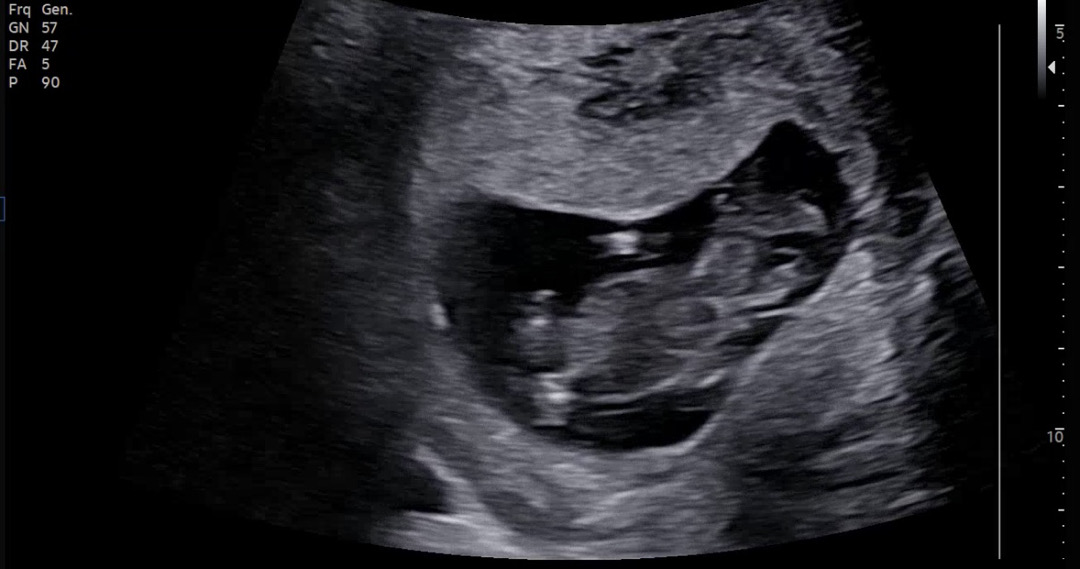

잘 안보이는거 같지만 각도법 궁금해요!

애기가 자꾸 뛰어가지구 이 사진밖에 못건졌는데 이걸로도 성별 추측할 수 있을까요??

딸같은데 반전되서 아들되는경우도있어요